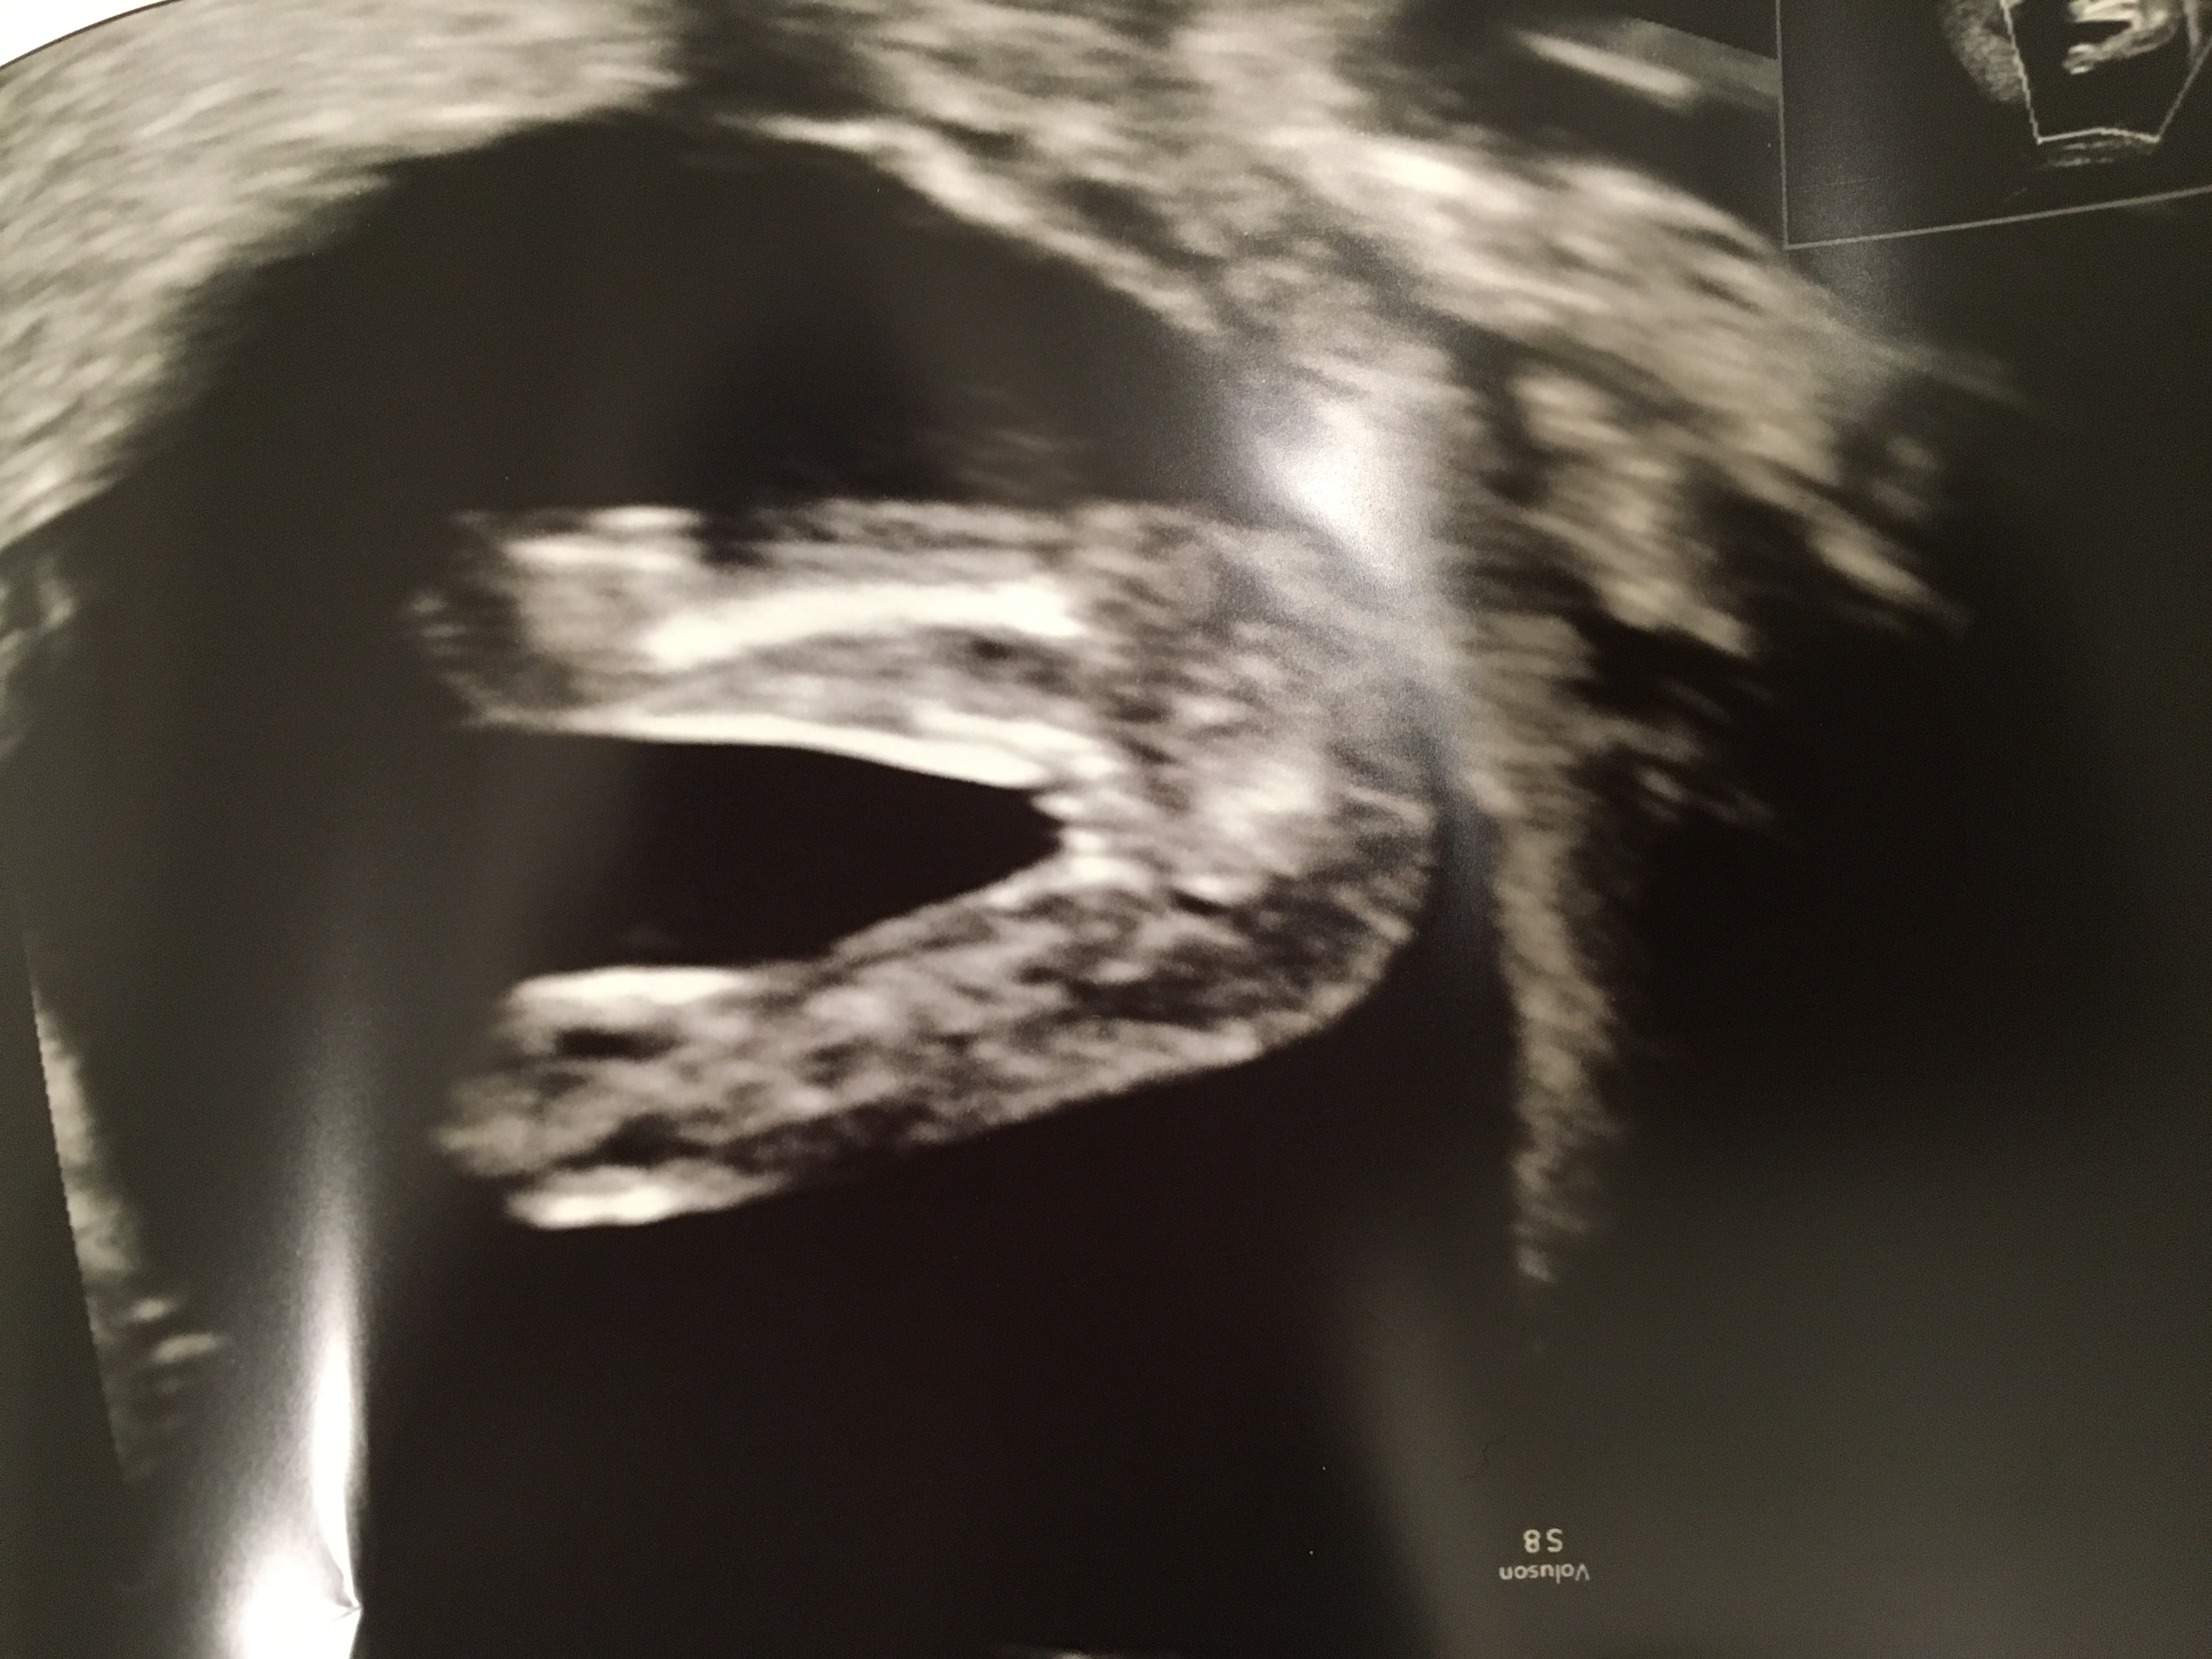

So I was on private UL,and they said "most likely" it is a girl. But then I see the the 3 D picture,and I see that there is like there is s lump in the middel of the legs. What do you think,based the 3 D and 2 D picture?

Attachment 34411Attachment 34412